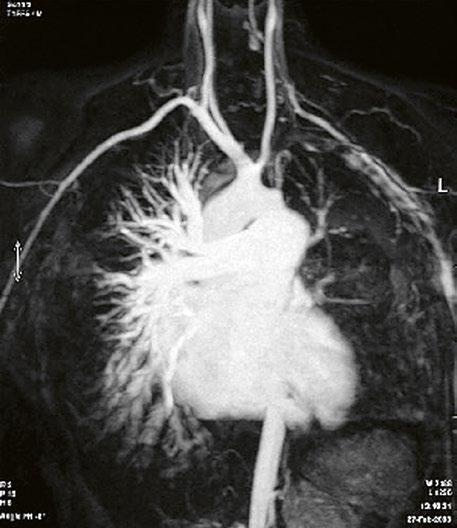

Při podezření na anomální návrat plicních žil je vhodnější doplnit CT angiografii nebo magnetickou rezonanci (Obr. 45.11, Obr. 45.12). Při podezření na závažnější plicní hypertenzi je indikovaná pravostranná katetrizace.

Obr. 45.12 CT angiografie s 3D rekonstrukcí u pacientky s defektem typu sinus venosus superior a s parciálním anomálním návratem dvou pravostranných plicních žil z horního a středního laloku do horní duté žíly, pravá dolní plicní žíla ústí normálně do levé síně